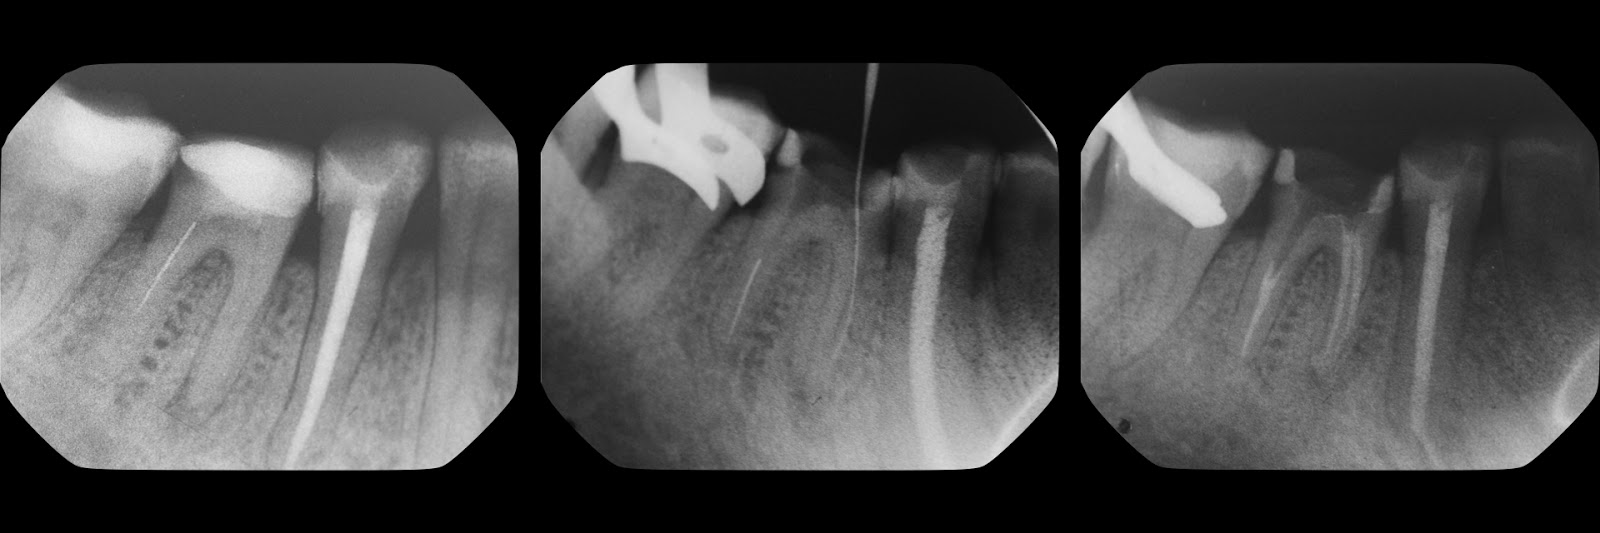

Фотографии стекловолоконных штифтов